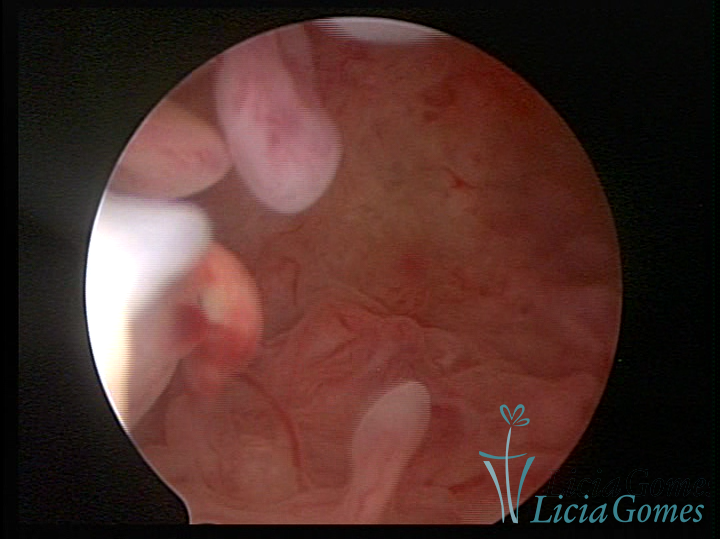

Este pode apresentar uma gama variável de aspectos macroscópicos, com aspecto pseudopolipoide; lembrando tecido cerebroide ou com reação deciduoide;a vascularização superficial é mais evidente e com vasos em formatos de saca-rolha ou espirais visualizando também a vascularização com atípias, com aumento do calibre dos vasos superficiais, pode ser encontrado também tecido em necrose, poderá haver um pequenos dendritos (papilomatoso).